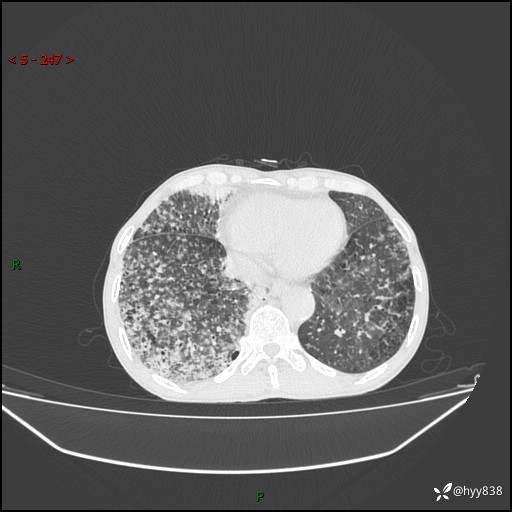

胸部CT平扫